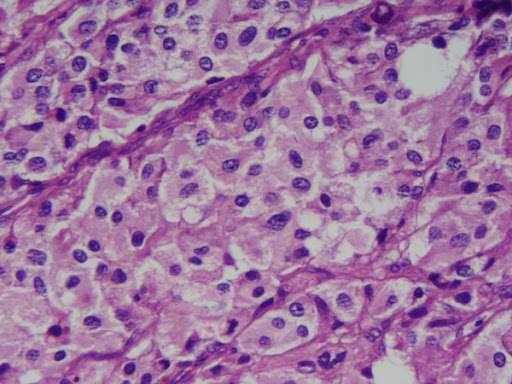

La enfermedad de von Hippel–Lindau tipo 2 es un síndrome hereditario autosómico dominante caracterizado por una predisposición a desarrollar diversos tumores benignos y malignos en múltiples órganos, entre ellos el feocromocitoma. Esta neoplasia, derivada de células cromafines productoras de catecolaminas en la médula suprarrenal, se presenta en aproximadamente un 30 % de los individuos portadores de la mutación a lo largo de su vida. La aparición puede darse tan temprano como a los 5 años de edad, aunque también puede manifestarse en la adultez, lo que obliga a una vigilancia clínica desde la infancia en portadores conocidos.

En el contexto del síndrome von Hippel–Lindau, los feocromocitomas presentan un comportamiento clínico distintivo en comparación con sus contrapartes esporádicas. Son significativamente menos propensos a la malignidad, con una tasa de transformación maligna estimada en un 3,5 %, frente a cerca del 10 % en pacientes sin esta enfermedad genética. Además, tienen una menor tendencia a diseminarse en comparación con los paragangliomas extraadrenales, cuya tasa de metástasis alcanza entre un 20 y un 25 %. Esta menor agresividad no elimina su potencial letal, pero sí modifica el enfoque diagnóstico y terapéutico.